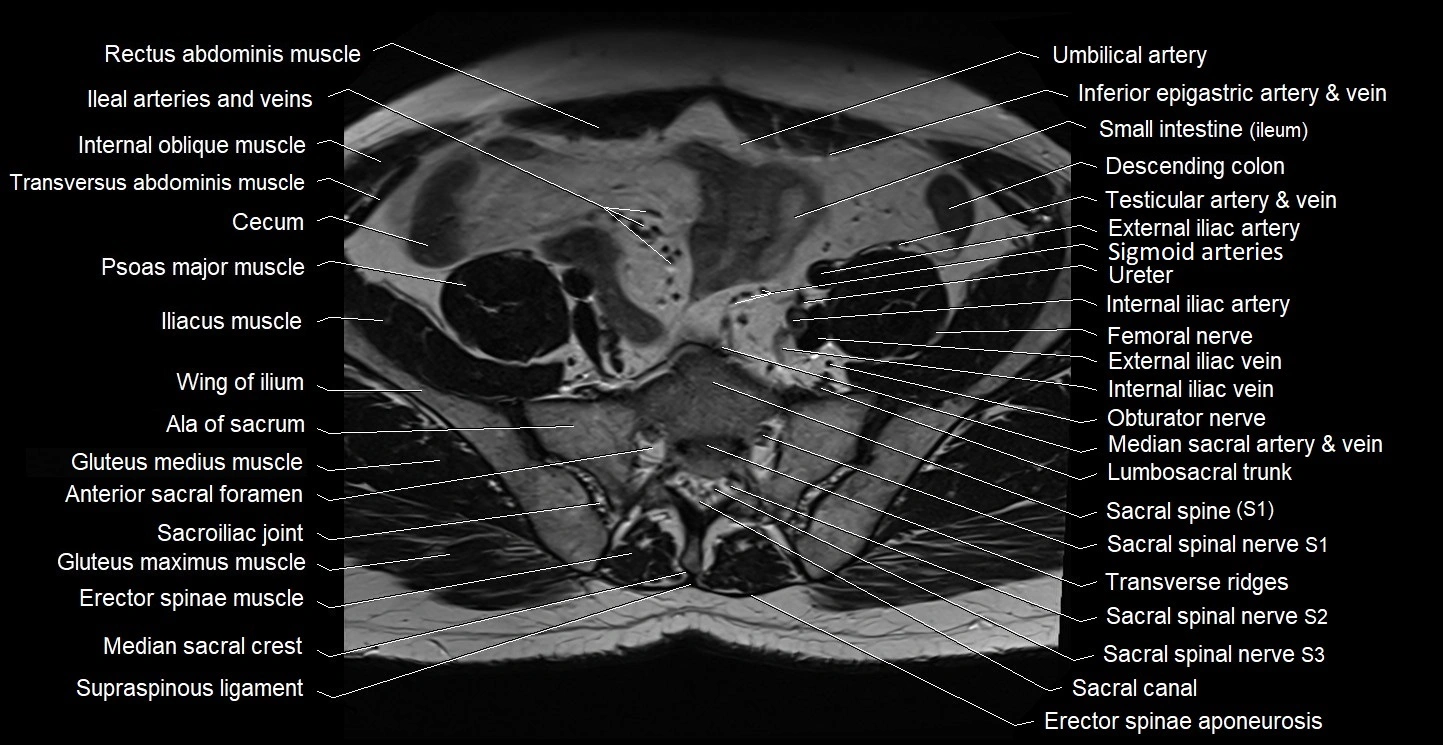

- Ala of sacrum

- Anterior sacral foramina

- Erector spinae muscles

- Exiting nerve root of spinal nerve S1

- Exiting nerve root of spinal nerve S2

- Exiting nerve root of spinal nerve S3

- External iliac artery

- External iliac vein

- Femoral nerve

- Gluteus maximus muscle

- Gluteus medius muscle

- Internal iliac artery

- Internal iliac vein

- Internal oblique muscle

- Lumbosacral trunk

- Median sacral crest

- Median sacral vein

- Obturator nerve

- Psoas major muscle

- Sacral canal

- Sacral plexus

- Sacroiliac joint

- Sacrum

- Sigmoid colon

- Spinal nerve S1

- Spinal nerve S2

- Spinal nerve S3

- Transverse ridges

- Transversus abdominis muscle

- Umbilical artery

- common iliac artery